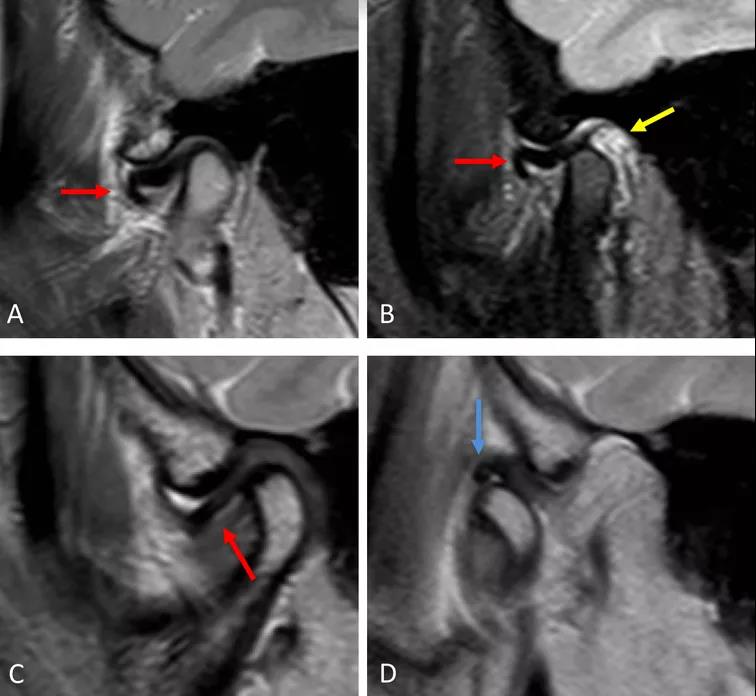

病例一:斜矢狀平面上的質(zhì)子密度加權(quán)圖像(PDWI)

A圖示:閉口位時(shí),顯示關(guān)節(jié)盤前移位明顯,雙凹形態(tài)消失。注意前帶的下移位(紅色箭頭)。

B圖示:張口位時(shí),顯示關(guān)節(jié)盤移位(紅色箭頭),關(guān)節(jié)積液(黃色箭頭)。病例2:斜矢狀平面上的質(zhì)子密度加權(quán)圖像(PDWI)

A圖示:閉口位時(shí),顯示下頜骨髁突前上側(cè)面硬化,前方扁平的椎間盤移位(紅色箭頭)。